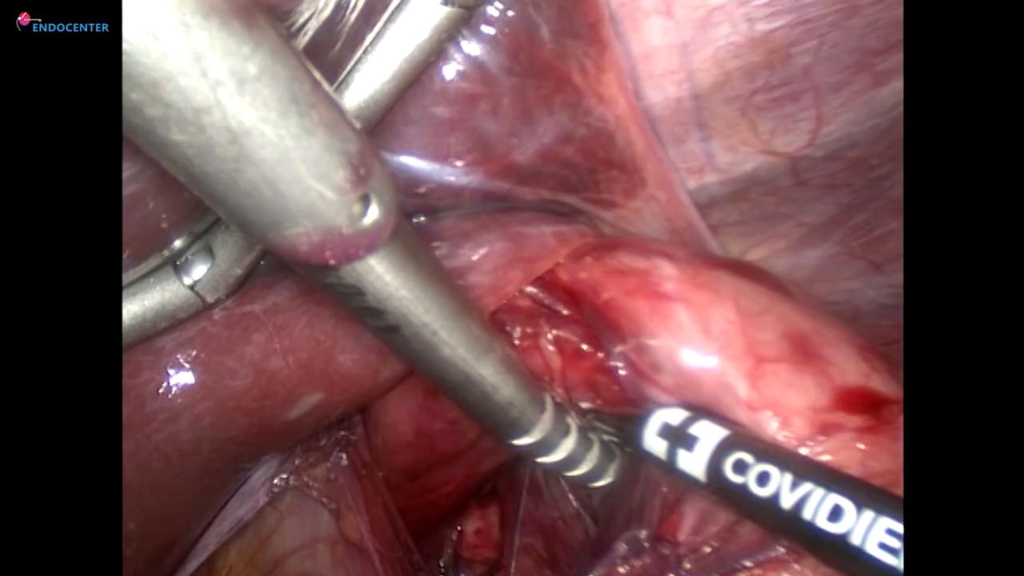

Laparoscopic Heller cardiomyotomy LIVE